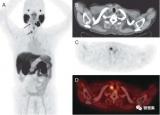

范日升:《和您一起认识PET/CT》

PET/CT是医院最高端的影像检查设备之一,一次显像可获得全身各部位的断层影像及功能信息,灵敏、准确、定位精确。PET/CT 是将正电子发射计算机体层显像(positron emission computed tomography,PET)与 X-计算机体层摄影(X-computed tomography,X-CT)整合为一体化,是功能显像和解剖显像的有机结合,在分子水平上显示组织细胞的代谢、功能、血流、细胞增殖和受体分布,广泛应用于肿瘤、心血管疾病、神经功能病变、淋巴系统疾病等方面,为临床提供疾病生理和 2022-08-16 PET/CT辐射成像

全身PET图像揭示人体对COVID的免疫反应

这项新发现是加州大学戴维斯分校和联合成像公司合作的结果。他们一起开发了世界上第一台全身PET/CT扫描仪。 2022-08-16 PET/CT